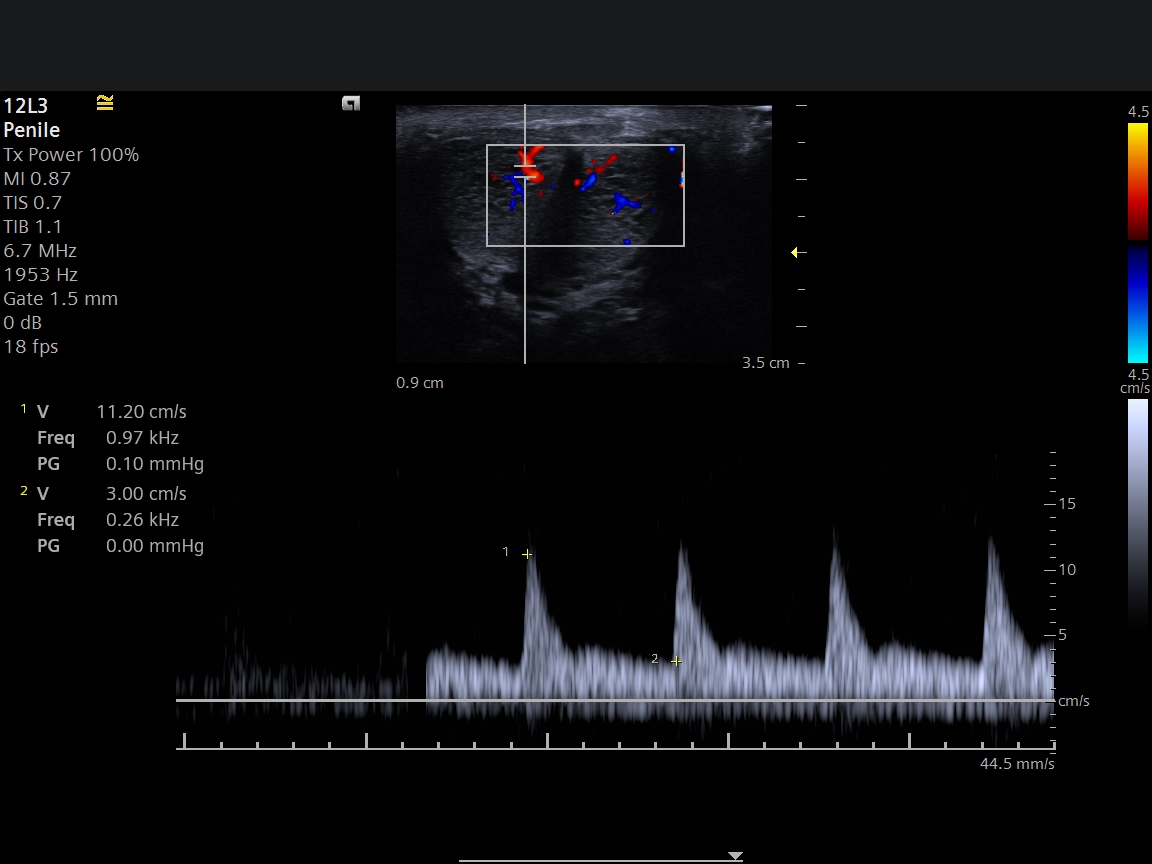

Penil Doppler ultrasonografi, penisteki damarların kan akımını değerlendiren özel bir ultrason incelemesidir.

- Kan akım hızları ölçülür

Bu ölçümler sayesinde penisteki arteriyel akım ve venöz sistem detaylı şekilde değerlendirilir.

Penil Doppler Sonuçları Ne Gösterir?

Penil Doppler incelemesi sonrasında genellikle üç farklı sonuç ortaya çıkabilir:

1️⃣ Normal damar yapısı

Penise gelen kan akımı normaldir.

2️⃣ Arteriyel yetmezlik

Penise gelen kan miktarı yetersizdir.

3️⃣ Venöz kaçak

Penis içine gelen kan yeterlidir ancak damar sistemi kanı tutamaz.

Bu sonuçlar tedavi planlamasında oldukça önemlidir.